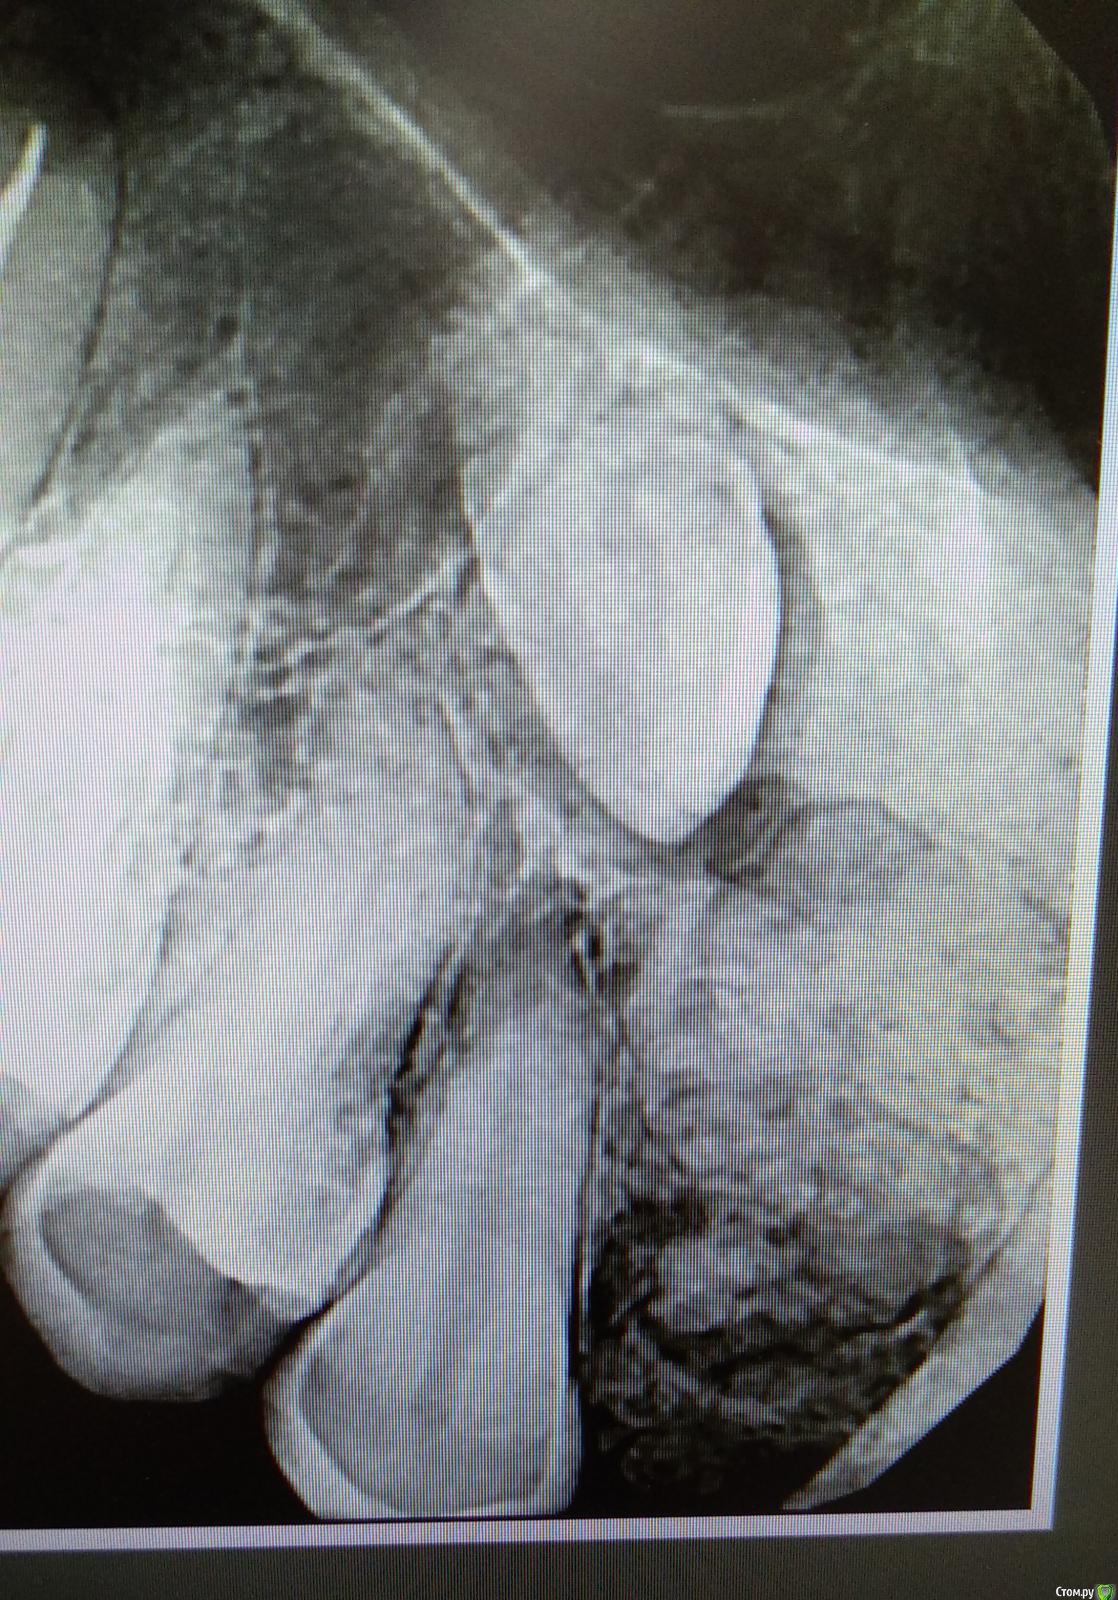

NickBulin Опубликовано 24 мая, 2018 Поделиться Опубликовано 24 мая, 2018 (изменено) Здравствуйте! Планировалась имплантация в области 1.2 зуба, кто нибудь сталкивался с подобной картиной?) В полости рта небольшое безболезненное уплотнение в проекции образования. Без кт, возможно ли предположить что это? Интересует дальнейшая тактика. Изменено 24 мая, 2018 пользователем NickBulin Ссылка на комментарий

Дмитрий Л. Опубликовано 24 мая, 2018 Поделиться Опубликовано 24 мая, 2018 Цементома. Ну или графт 1 Ссылка на комментарий

NickBulin Опубликовано 25 мая, 2018 Автор Поделиться Опубликовано 25 мая, 2018 (изменено) На кт направил сразу. Ретенция 1.2. На его месте последние 10 лет носился съёмный протез "бабочка". Изменено 25 мая, 2018 пользователем NickBulin Ссылка на комментарий